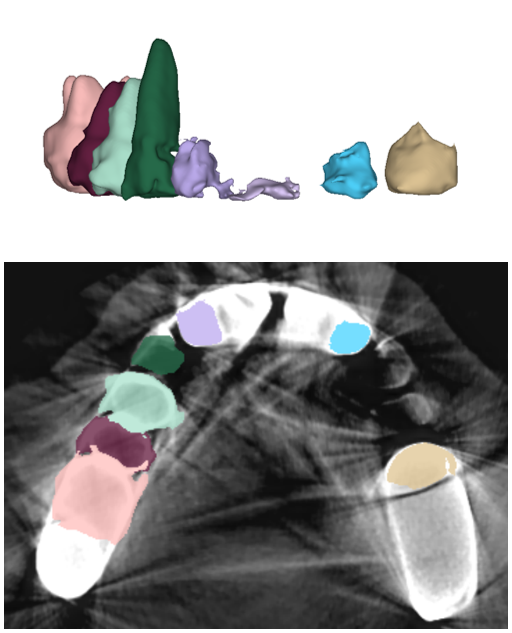

Digitized orthodontic applications in dentistry have increased based on the development of cone beam computed tomography (CBCT) imaging. CBCT is a widely used medical imaging technique that provides high resolution 3D volumetric data. To build an effective computer-aided diagnosis system in orthodontic applications, such as oral treatment planning for tooth reformation and implant guide simulation, automatic segmentation of individual teeth from the CBCT images is an essential prerequisite (Fig. 1). However, accurate segmentation of an individual tooth from a CBCT image is a challenging task owing to heterogeneous intensity distribution, unclear boundaries between the tooth root and alveolar bone (Fig. 2a), and diverse shapes and poses. Moreover, the majority of CBCT images contain severe metal artifacts that hinder the accurate segmentation of teeth (Fig. 2b). In this study, we propose a fully automated instance segmentation framework using 3D images of teeth that is robust to several challenging conditions of the teeth, such as, dynamic poses, missing teeth, inter-tooth proximity, and presence of severe metal artifacts.

In this study, we propose a fully automatic, hierarchical method that performs accurate individual tooth detection followed by a CNN based on single pixel-wise labeling to segment the tooth (Fig. 3). We first extracted the volume-of-interest (VOI) region by pose regression using neural networks. Then, the extracted VOI region was realigned based on the pose (i.e., axes). Subsequently, we detected individual teeth and performed individual tooth segmentation. The key components of our method are the accurate tooth detection framework through VOI realignment, which reduces the inter-overlapping area between boxes, multiclass classification within a detector, which boosts the accuracy of metal-tooth detection, and the metal-robust CNN for accurate tooth segmentation.

The proposed individual tooth segmentation method comprises of three steps: VOI realignment, tooth detection, and individual segmentation. The VOI realignment is primarily performed by a pose regression in a projected 2D space (i.e., x-axis-directional projection). The realignment of VOI not only crops the interested region but also aligns the primary axes of the teeth to be better aligned to the image axes. Subsequently, tooth detection and segmentation are performed using CNNs. The details of the algorithm are described in the following subsections.

The manual seeded level-set methods [6, 7] demonstrate inferior performances while segmenting teeth with predominant metal artifacts (Table II). The energy-based (i.e., level-set function) algorithmic approach failed while defining an optimum stopping criterion (Fig. 12b). The AJI measures for level-set methods are omitted because the box detectors do not exist in the level-set-based methods. In particular, the low precision and sensitivity values indicate that level-set methods have over-segmented or under-segmented the teeth in many cases (Figs. 12b and 13a). The accuracies of the Mask-RCNN [17] and ToothNet [11] showed comparable performance to the level-set-based methods. The instance segmentation framework successfully detected and segmented the teeth automatically. However, it failed to detect all the teeth regions accurately, which resulted in a degradation of the segmentation performance. Moreover, the performance of the segmentation itself also showed low accuracy owing to the metal artifacts (Figs. 12c and 12d). Figure 13 illustrates the more severe conditions of metal artifacts. The performance of the detection and segmentation processes significantly degraded in ToothNet [11] (Fig. 13b) and Mask-RCNN [17] (Fig. 13c). Conversely, our proposed method outperformed the other state-of-the-art methods (Figs. 12e and 13d); further, the comparison between the PA- and non-PA-based results also demonstrated that the employment of a PA detector significantly improved the proposed architecture (Table II). The superior AJI value clearly shows that successful detection improved the overall performance.